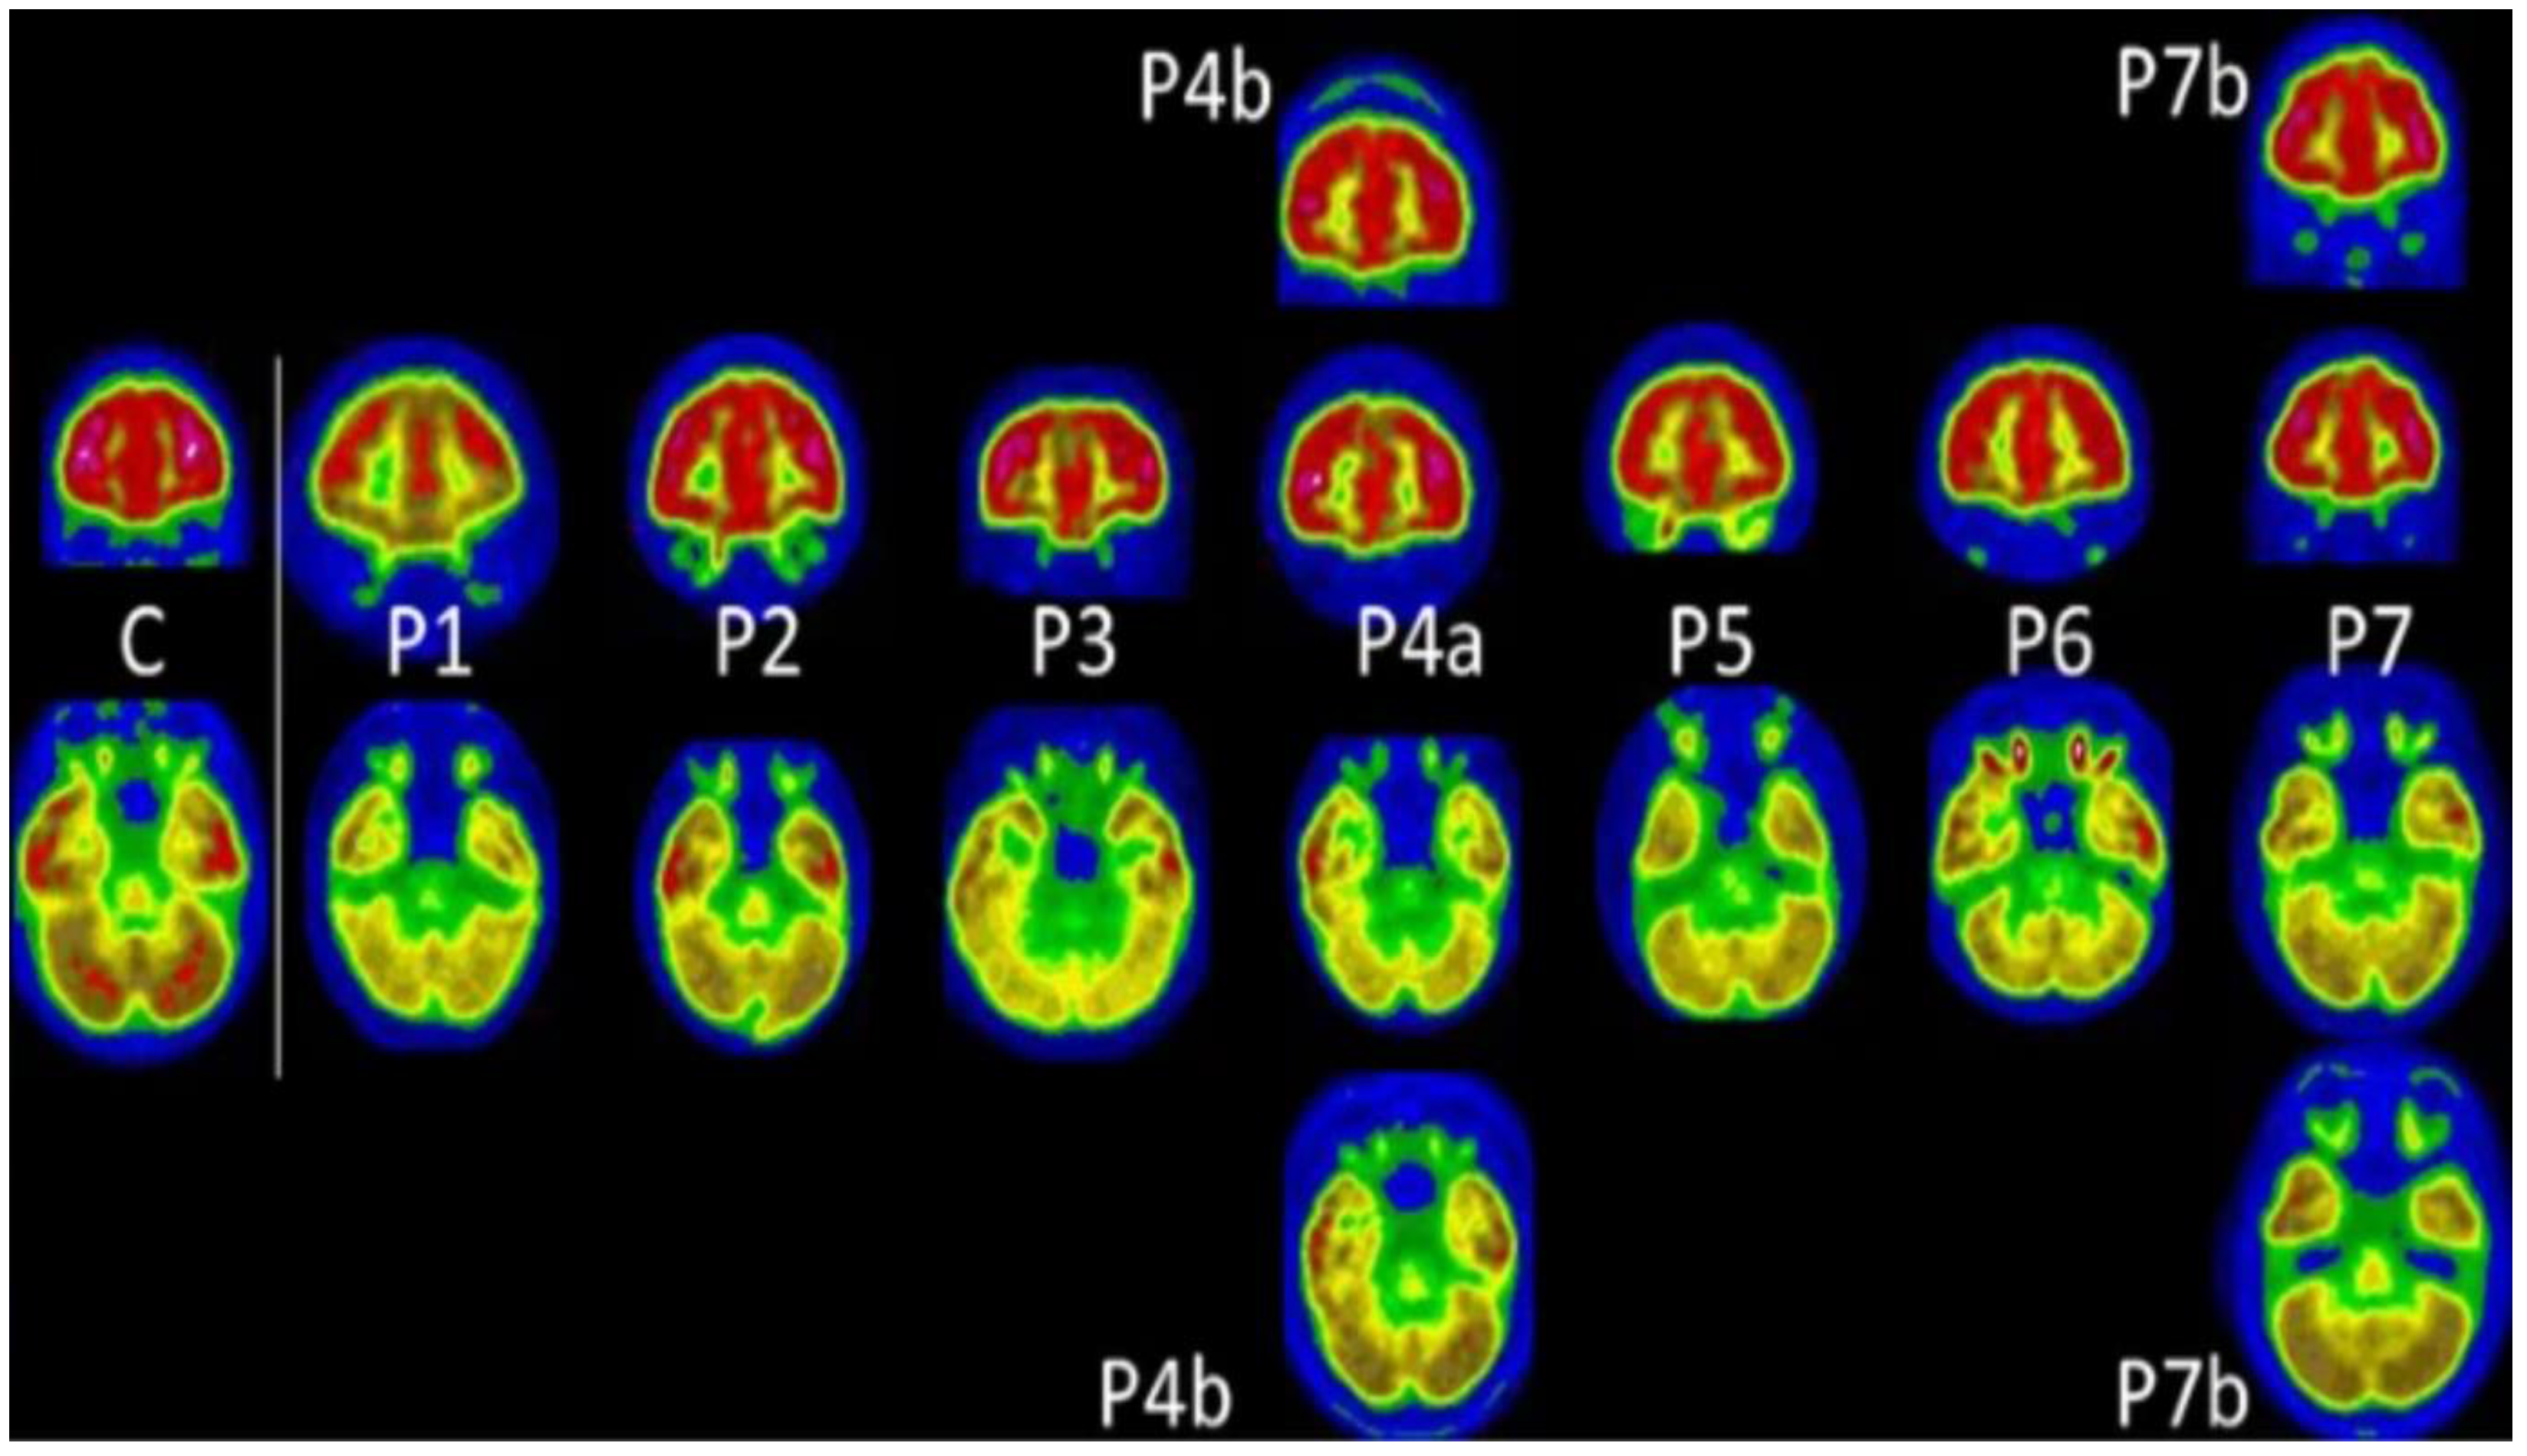

| Guedj et al. [44] | Bilateral rectal/orbital gyrus, including the olfactory gyrus; the right temporal lobe, including the amygdala and the hippocampus, extending to the right thalamus; the bilateral pons/medulla brainstem; the bilateral cerebellum | Shortness of breath, chest pain, muscular pain, memory cognitive complaints, insomnia, hyposmia/anosmia, dysgeusia/ageusia | Approximately 97 days | Retrospective/35 subjects (15 males and 20 females; 12 had history of hospitalization in the ICU) |

- Guedj, E.; Million, M.; Dudouet, P.; Tissot-Dupont, H.; Bregeon, F.; Cammilleri, S.; Raoult, D. 18F-FDG Brain PET Hypometabolism in Post-SARS-CoV-2 Infection: Substrate for Persistent/Delayed Disorders? Eur. J. Nucl. Med. Mol. Imaging 2021, 48, 592–595. [Google Scholar] [CrossRef] [PubMed]